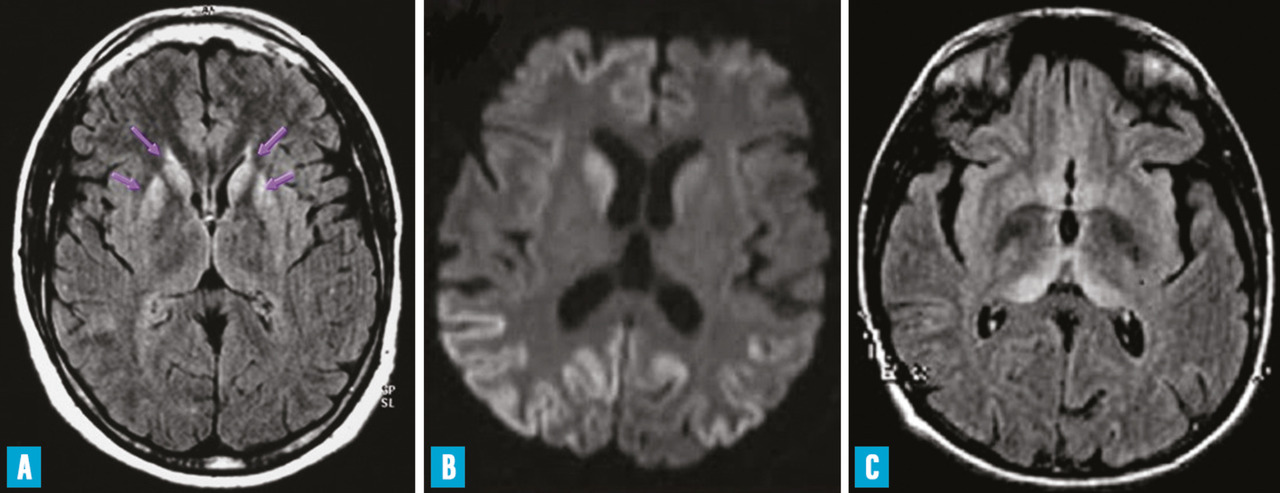

L’observation sur l’imagerie par résonance magnétique (IRM) d’hyper­signaux dans les noyaux gris centraux ou dans le cortex cérébral, sur les séquences T2, FLAIR ou de diffusion avec une diminution du coefficient de diffusion apparent de l’eau (ADC) est fréquente (fig. 1 A et B). Il n’existe pas de prise de contraste.

La vMCJ débute par des troubles psychiatriques (dépression sévère, état délirant, hallucinations…) ou des douleurs. Le diagnostic n’est évoqué que quelques semaines plus tard, quand apparaissent l’ataxie cérébelleuse, le syndrome pyramidal ou les myoclonies. L’atteinte intellectuelle est plus tardive. L’évolution se fait vers le mutisme akinétique. Le décès survient après quinze mois en moyenne. L’EEG n’est pas périodique. La protéine 14 - 3 - 3 n’est détectable que dans la moitié des cas ; la RT-QuIC est en règle négative. Des hypersignaux sur l’IRM cérébrale sont fréquemment observés dans les noyaux pulvinar et dorsomédian du thalamus ; ils ont une importante valeur diag­nostique (fig. 1C).10 En raison de son accumulation dans les organes lymphoïdes, la PrPsc peut être mise en évidence sur une biopsie d’amygdale pharyngée. L’étude du gène PRNP ne décèle pas de mutation, tous les patients sont M/M au codon 129 excepté le dernier patient britannique décédé en 2016 qui était M/V. L’étude neuropathologique permet d’observer des plaques PrPsc particulières dites florides (plaques amyloïdes entourées de spongiose). Le profil de migration en western blot de la PrPsc est identique à celui de la PrPsc bovine (type 2B).